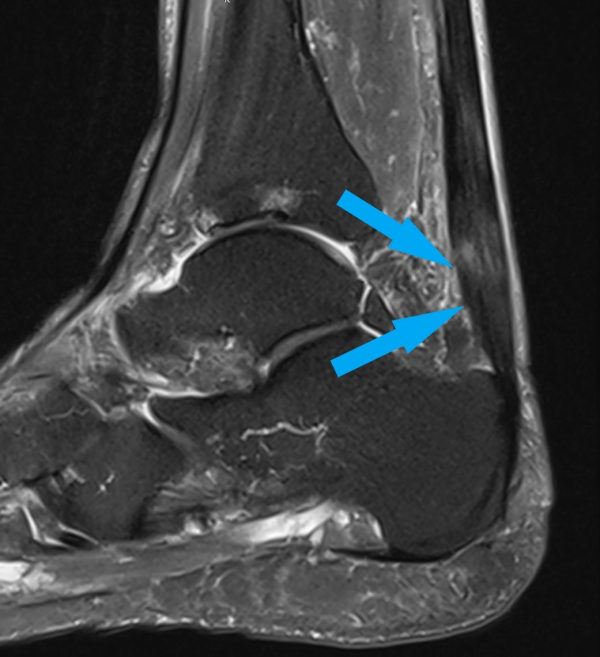

ausgeprägte Achillodynie mit Strukturdefekt in der Achillessehne